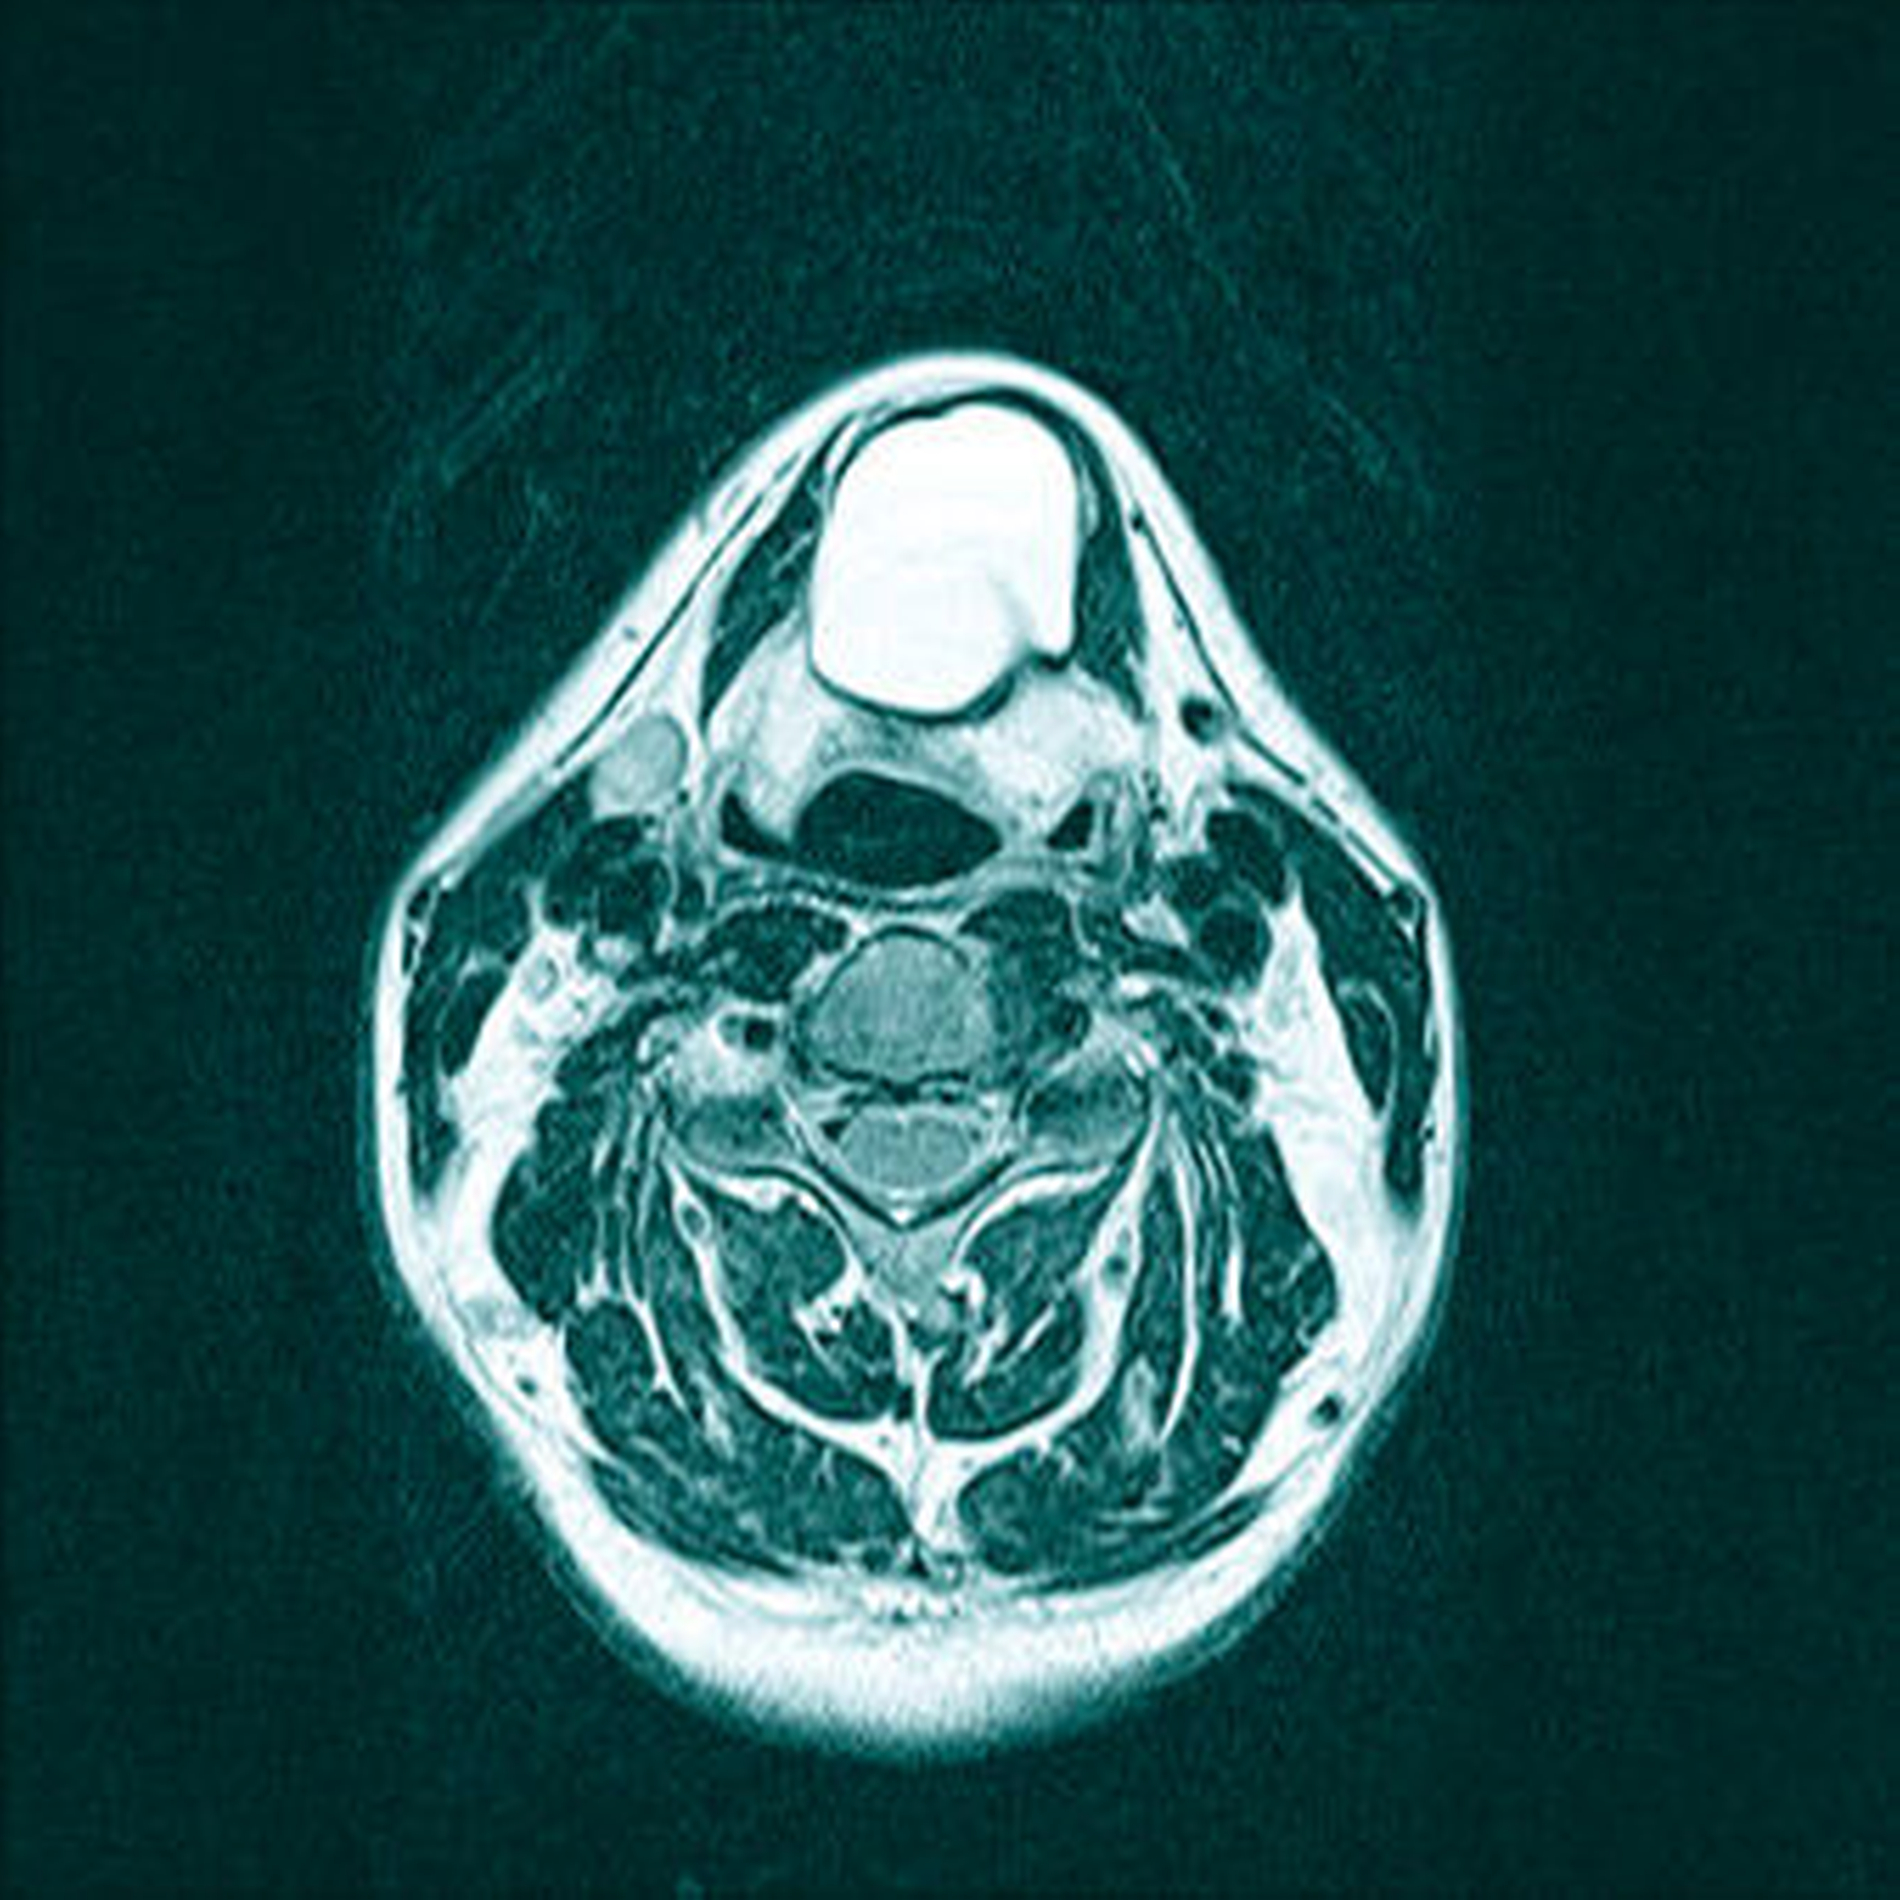

Die unter ambulanten Bedingungen angefertigte schnittbildgebende MRT-Untersuchung des Halses zeigte eine 41×35×27 mm große, gut abgrenzbare und abgekapselte Raumforderung mit homogener Binnenstruktur. Die Dichtewertmessung wies anhand der Verteilung der Hounsfield-Einheiten einen mit flüssigkeitsäquivalentem Gewebe, gefüllten Hohlraum auf (Abbildung 2a). Dieser war mit einer mittigen Einschnürung in der Medianebene des Halses und in der Mitte des Os hyoideum lokalisiert (Abbildung 2b). Dabei werden die Verdrängung des aerodigestiven, benachbarten Raumes sowie die Anhebung des Mundbodens und der Zungengrundmuskulatur deutlich (Abbildung 2c).